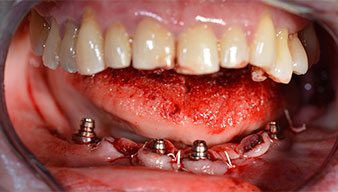

After removal of the residual dentition in the mandible, the alveolar crest was exposed from 37 to 47.

The mental foramen was first identified as a limiting anatomical structure and then the cortical bone of the crest was smoothed with the straight handpiece and a large rose-head bur (Fig. 4).

Angled abutments (35°) were screwed in to compensate for the divergence of the distal implants, with the result that the emergence profile of all implants was as perpendicular as possible to the bite plane. This is a prerequisite for occlusal placement of the provisional and subsequently the permanent denture (Fig. 15 and 16).

The impression and bite registration were then performed so that the dental technician could begin producing the provisional restoration immediately. This was then screwed in on the same day (Fig. 17 and 18).